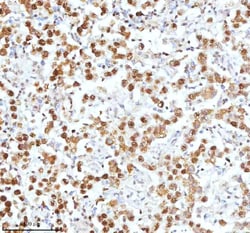

Reconstitute with 0.2 mL of distilled water to yield a concentration of 500 μg/mL. Positive Control - WB: human LNCAP whole cell, human Hela whole cell, human 293T whole cell, human HepG2 whole cell, human Jurkat whole cell, human K562 whole cell, human A549 whole cell, human A431 whole cell. IHC: human bladder cancer tissue, human bladder cancer tissue, human colon adenocarcinoma tissue, human colon adenocarcinoma tissue, human glioblastoma tissue, human glioblastoma tissue, human liver cancer tissue, human liver cancer tissue, human lung adenocarcinoma tissue, human lung adenocarcinoma tissue, human pancreas ductal adenocarcinoma tissue, human pancreas ductal adenocarcinoma tissue, human testicular seminoma tissue, human testicular seminoma tissue. ICC/IF: U2OS cell. Flow: A431 cell. Store at -20°C for one year from date of receipt. After reconstitution, at 4°C for one month. It can also be aliquotted and stored frozen at -20°C for six months. Avoid repeated freeze-thaw cycles.